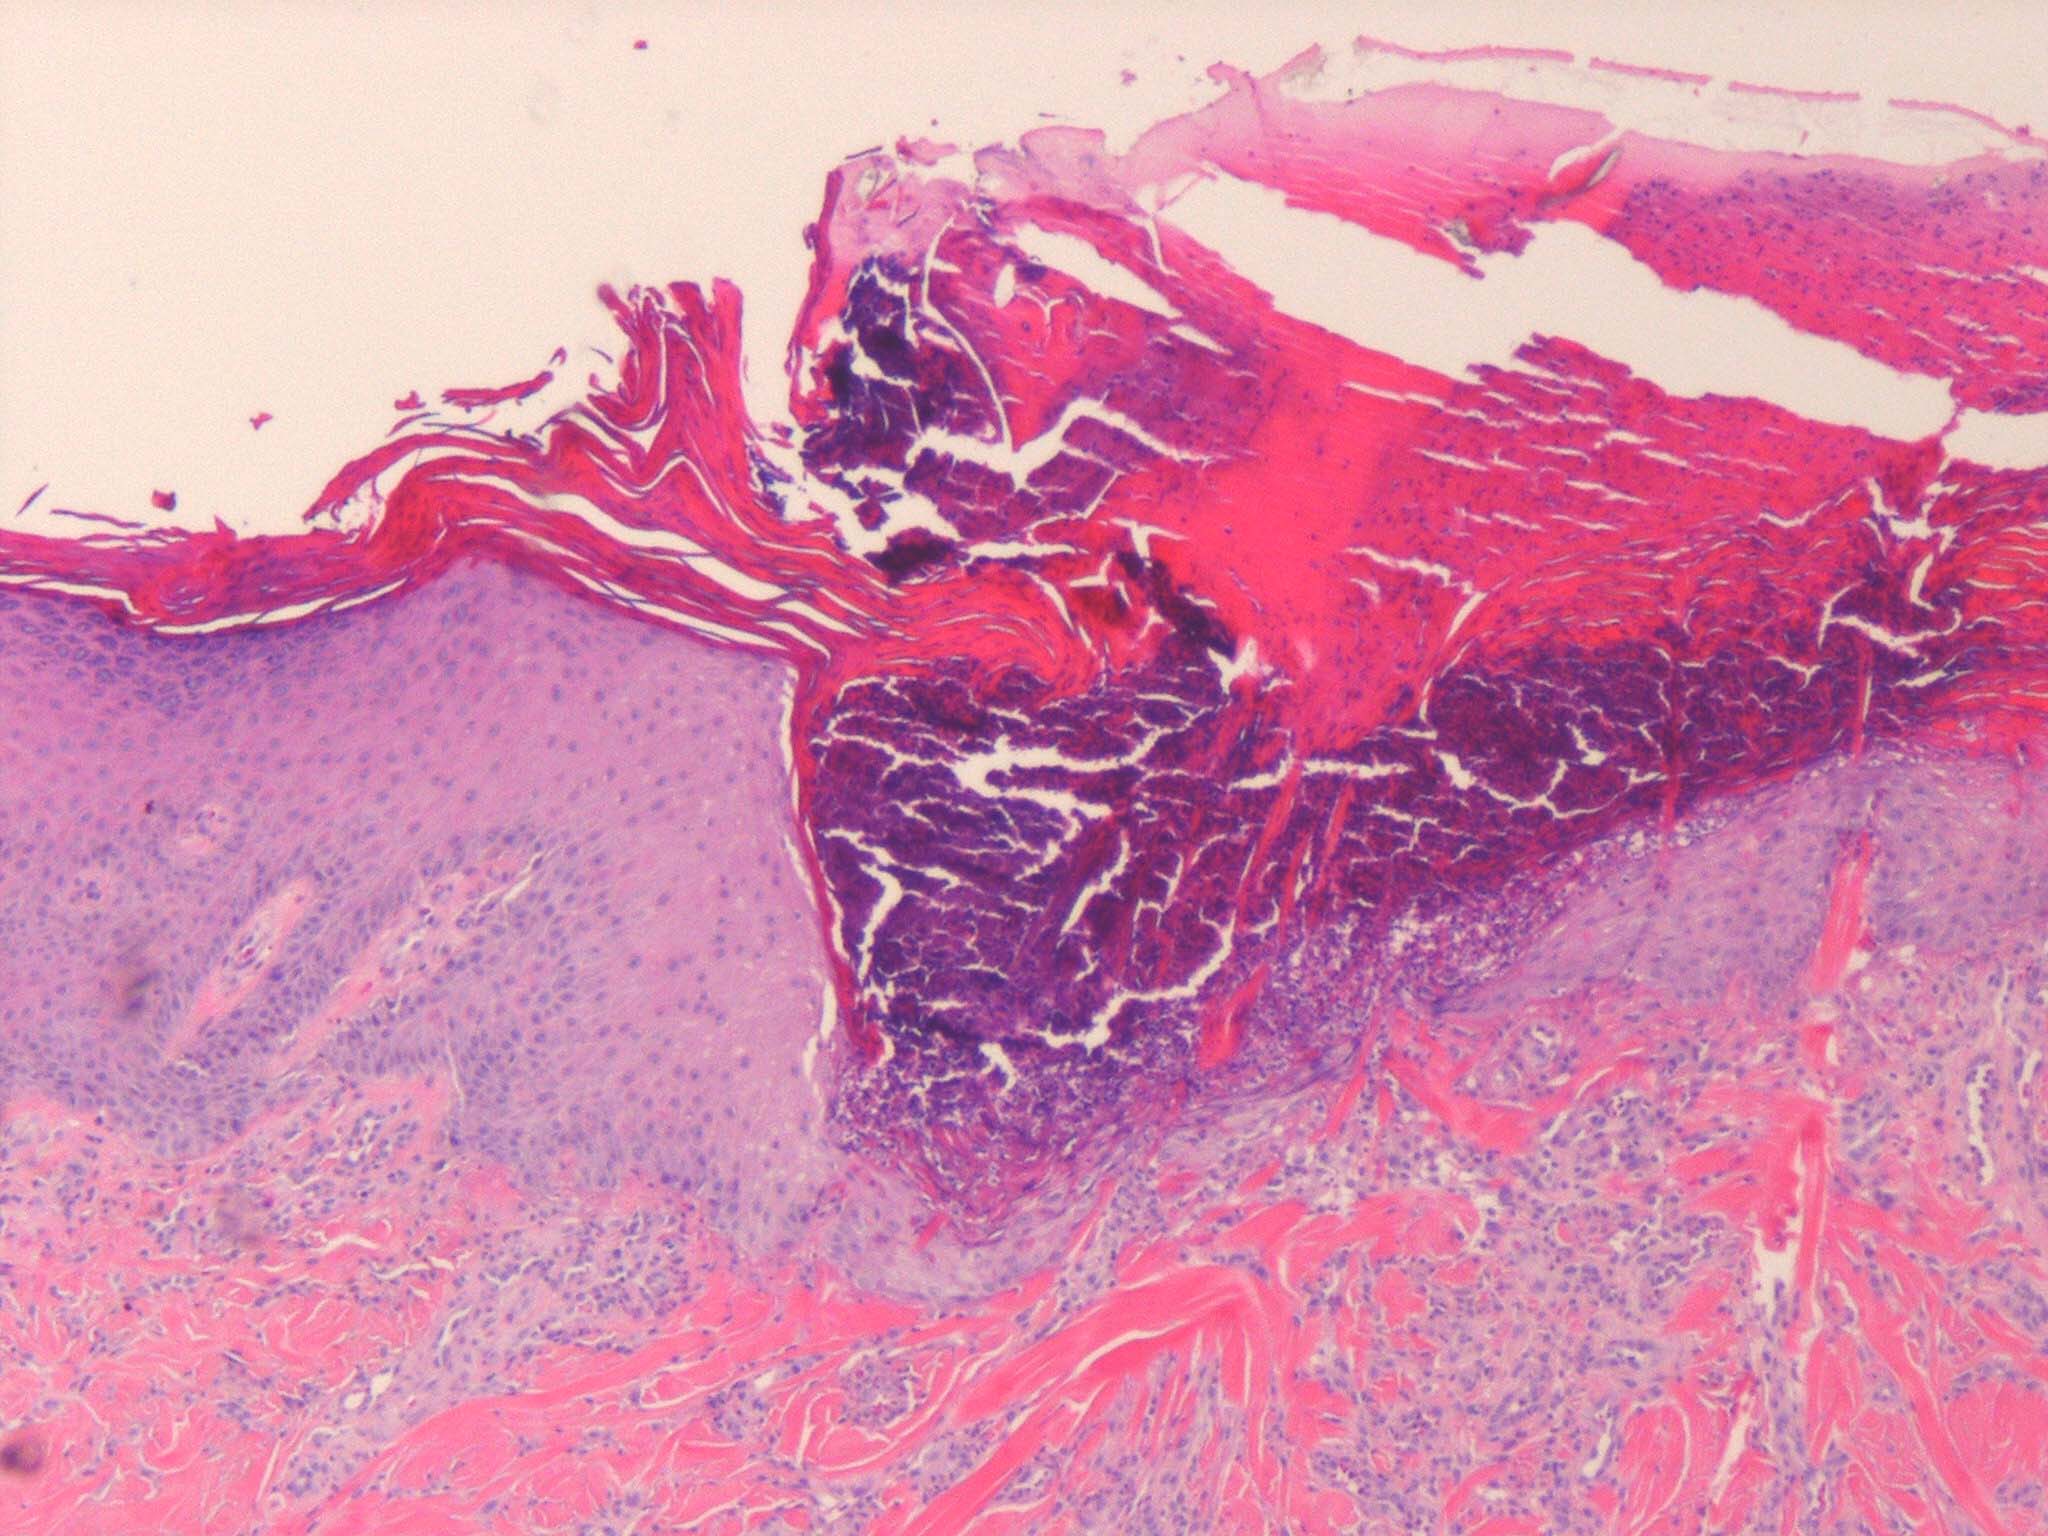

The histology varies with the stage of the reactive perforating collagenosis. Early lesions show epidermal hyperplasia associated with underlying degenerate basophilic collagen fibers. In established lesions, a cup-shaped depression of the epidermis associated with a keratin plug containing parakeratosis, inflammatory debris and collagen fibers can be seen.

Vertically orientated basophilic collagen fibers are seen in the underlying dermis, with focal extrusion through the epidermis

The epidermis is atrophic and may show ulceration. However, at the edges of the cup-shaped invagination, the epidermis is hyperplastic. Additionally, a mild perivascular lymphohistiocytic infiltrate can be seen.